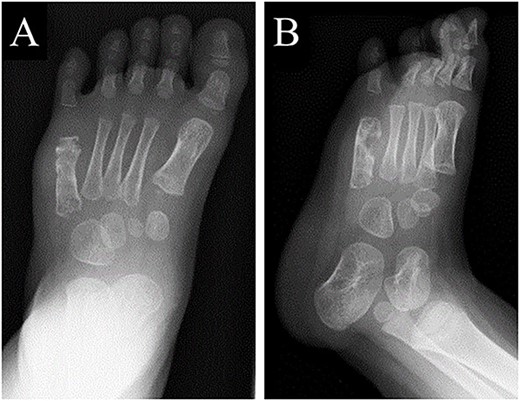

A 21-month-old Japanese female infant presented with a swollen mass on the dorsolateral aspect of the left foot. Her parents noticed the mass and brought the patient to our hospital. The patient had no past medical histories or complications prior to the occurrence. In addition, she received the BCG vaccine at the age of 4 months in Japan. At first visit to our hospital, physical examination revealed the ~3 × 3 cm mass was located on the dorsolateral aspect of the left foot and was hard accompanied by local heat (Fig. 1). Plain radiographs of the left foot showed a lytic lesion without periosteal reaction in the fifth metatarsal bone (Fig. 2). Magnetic resonance imaging (MRI) showed an isointense lesion on T1-weighted images and a hyperintense lesion on T2-weighted images around and within fifth metatarsal (Fig. 3). Gallium scintigraphy revealed intense uptake in the patient’s left foot (Fig. 4). In addition, laboratory examination was within normal. Based on medical history, clinical and imaging findings, we considered the possibility of neoplasia or osteomyelitis and performed an open debridement and biopsy of the lesion to make a diagnosis. The lesion was yellow and consisted of weak, adipose-like tissue that surrounded and continued into the inferior of the fifth metatarsal bone (Fig. 5). The lesion inside and outside the bone was resected as much as possible. Histopathologic examination of the lesion showed granulomatous inflammation including anaplastic giant cells, Langerhans-type giant cells and caseous necrosis (Fig. 6). Based on these results, TB or BCG osteomyelitis was considered as a diagnosis. The tuberculin test was positive, but the QuantiFERON TB test was negative. In addition, samples analyzed using polymerase chain reaction did not identify M. tuberculosis, but did identify the BCG Tokyo-172 strain. Per these findings, the patient was diagnosed with BCG osteomyelitis of the fifth metatarsal and oral treatment with anti-TB medicine including isoniazid (100 mg/day) and rifampicin (150 mg/day) was started. Clinical findings included reduction in swelling of the mass and gradual remodeling of the lytic lesion of the fifth metatarsal on plain radiographs (Fig. 7). However, 10 months after starting the anti-TB treatment, the mass recurred, and MRI revealed a residual high-intensity lesion around and inside the fifth metatarsal on T2-weighted fat-suppressed images (Fig. 8). It was determined that the lesion was difficult to control with anti-TB treatment alone, so an open debridement for the lesion was performed again. Histopathologic examination of the lesion revealed an epithelioid granuloma with necrosis. Therefore, the anti-TB treatment was continued. Six months after the second surgery, clinical and radiographic image findings showed complete improvement (Fig. 9). As a result, anti-TB treatment was ended. At the time of writing this report, 8 years after starting anti-TB treatment, there has been no recurrence.

At 6 months after the second surgery, image findings on plain radiographs completely improved on (A) anteroposterior and (B) oblique views.